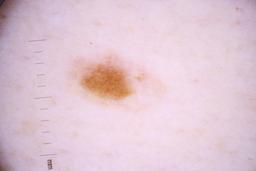

ISIC_4077341

- Challenge 2020: Training

- IP_1969685 IL_9238622

Clinical

| Field | Value |

|---|---|

| acquisition_day | 1 |

| age_approx | 50 |

| anatom_site_1 | Trunk |

| anatom_site_2 | Anterior trunk |

| concomitant_biopsy | False |

| dermoscopic_type | contact non-polarized |

| diagnosis_1 | Benign |

| diagnosis_confirm_type | serial imaging showing no change |

| family_hx_mm | False |

| image_type | dermoscopic |

| lesion_id | IL_9238622 |

| patient_id | IP_1969685 |

| personal_hx_mm | True |

| sex | male |